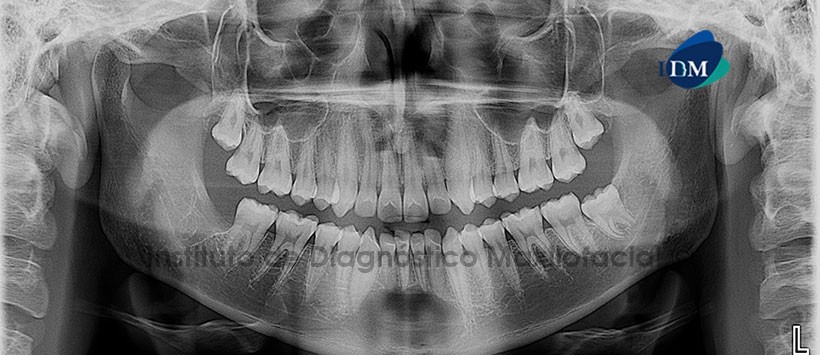

Paciente masculino, 17 años de edad, es referido al Instituto de Diagnostico Maxilofacial (IDM) para evaluación general.

A la evaluación de la radiografía panorámica, se aprecia una imagen radiolúcida unilocular de límites definidos y bordes no corticalizados, localizado en la sínfisis mandibular a nivel apical de las piezas antero-inferiores, extendiéndose hacia el reborde basal mandibular (Figura 1). Se decide ampliar el estudio por medio de una tomografía volumétrica (CBCT), para una mejor visualización de la posible lesión.